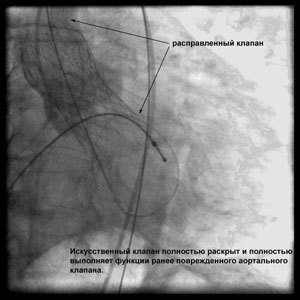

Через прокол (или маленький разрез) в артерии, в сжатом состоянии проводят искусственный клапан, который расширяется при его установке на месте поврежденного аортального клапана. После раскрытия клапан начинает функционировать и восстанавливает полноценную и нормальную работу аорты.